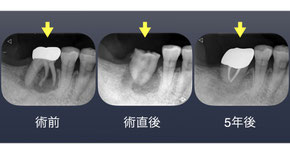

「右下の歯が腫れた」

右下第一大臼歯を抜歯し近心根(前方の根)を遠心根へ移植した。